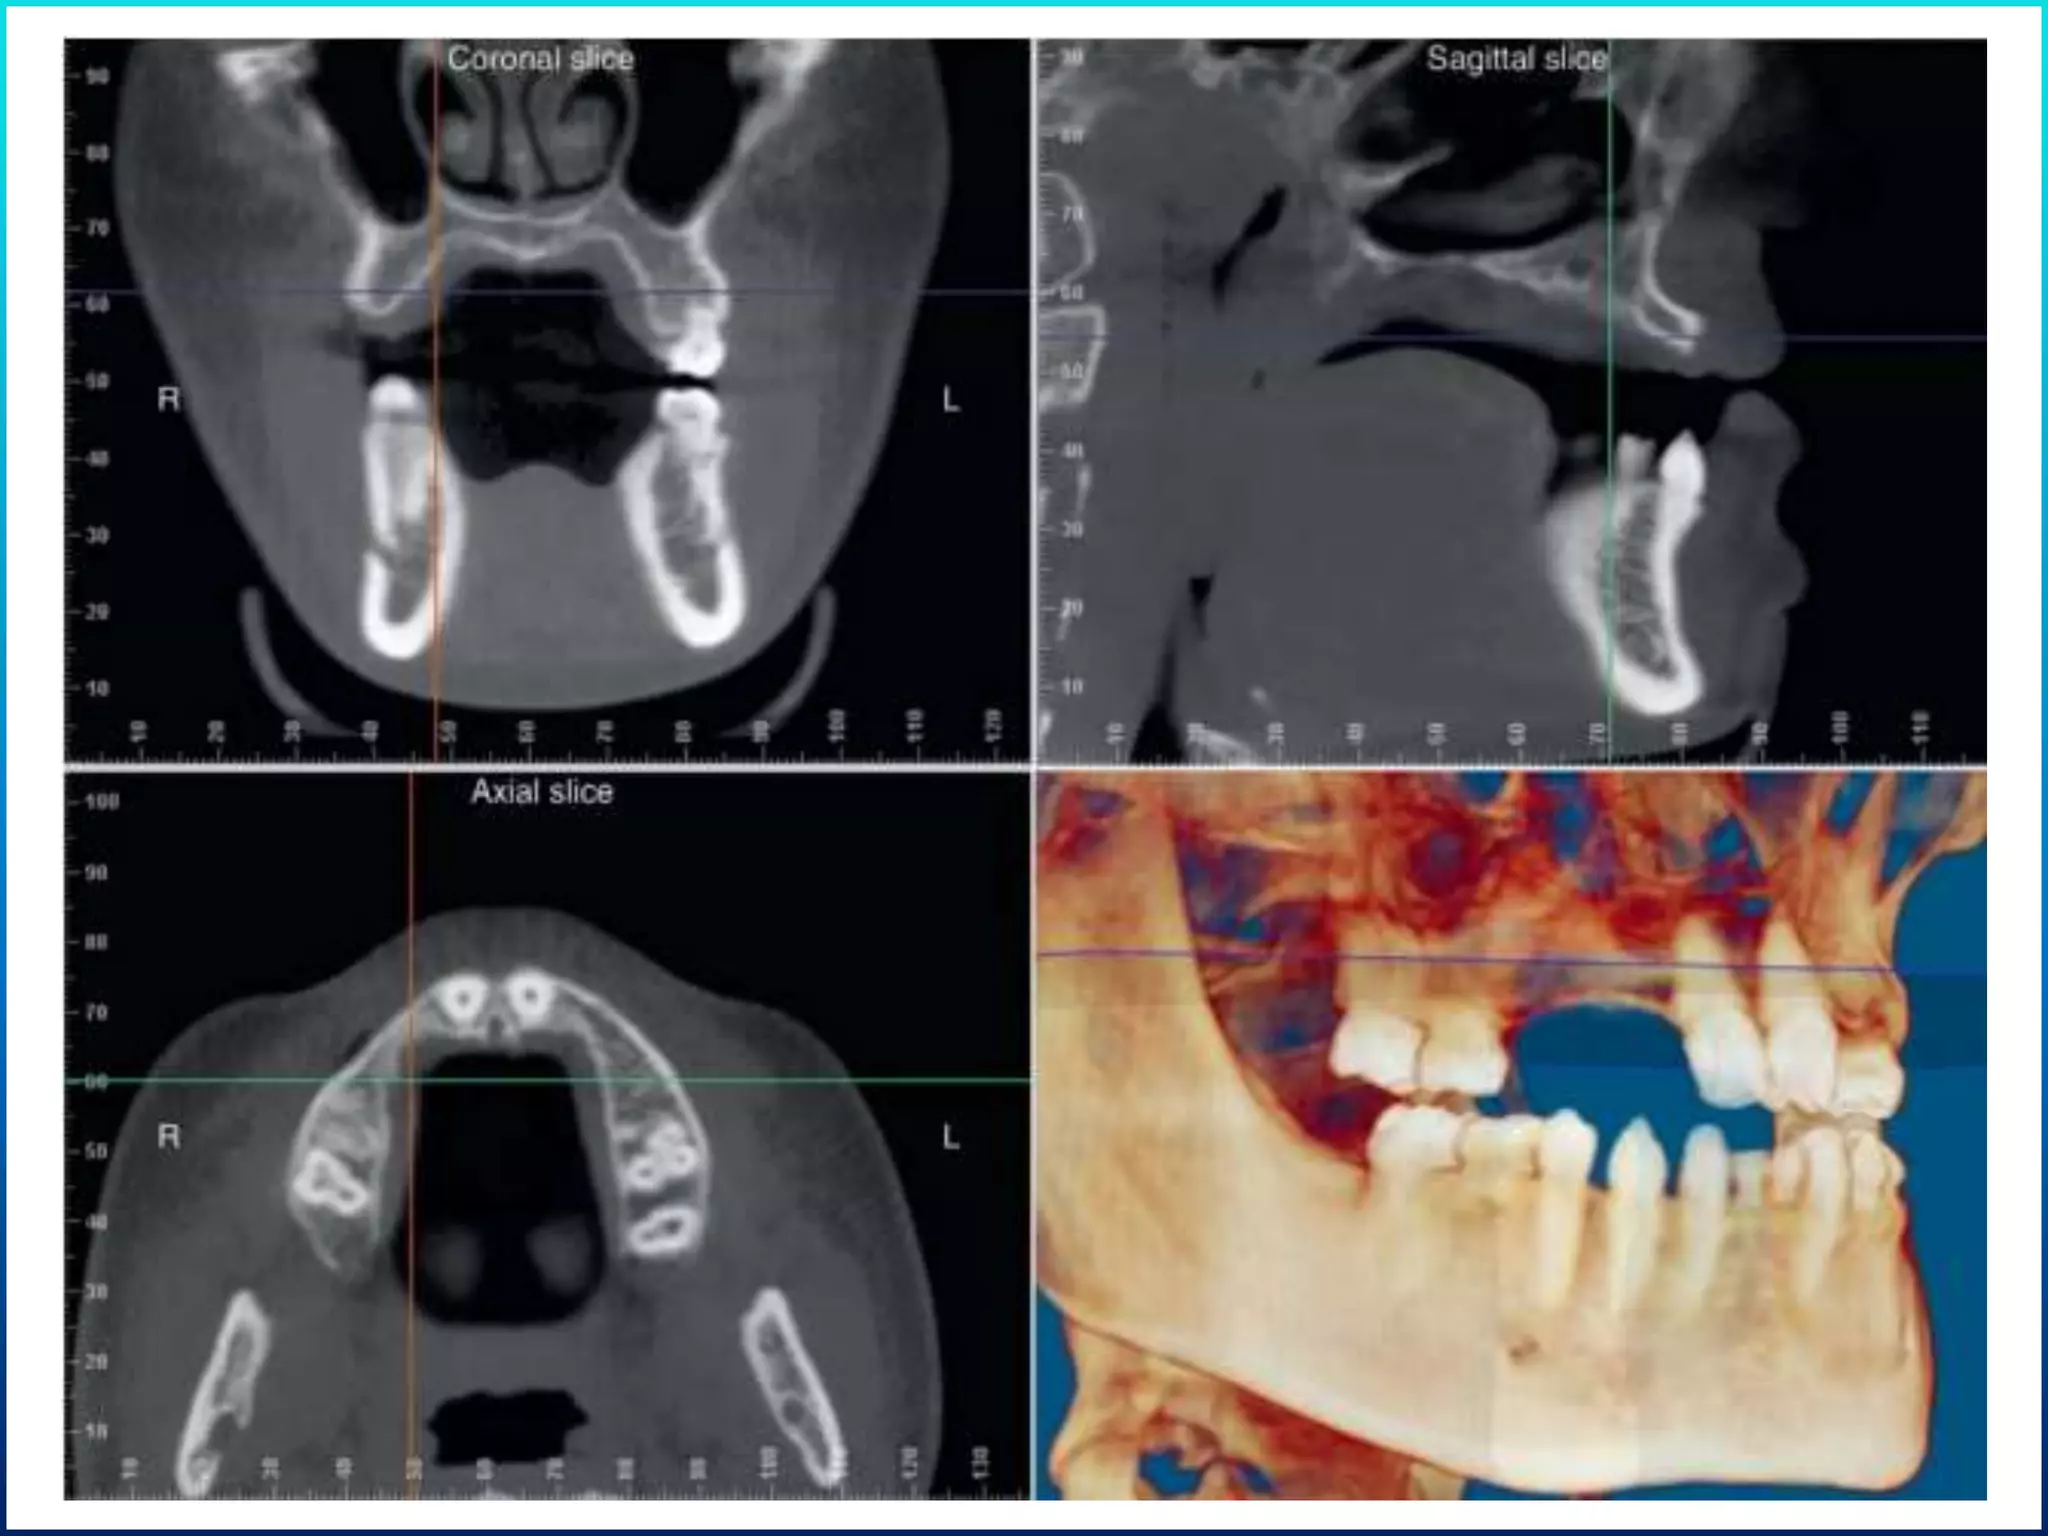

Diagnosis and treatment planning

 Bone mapping

 Diagnostic imaging